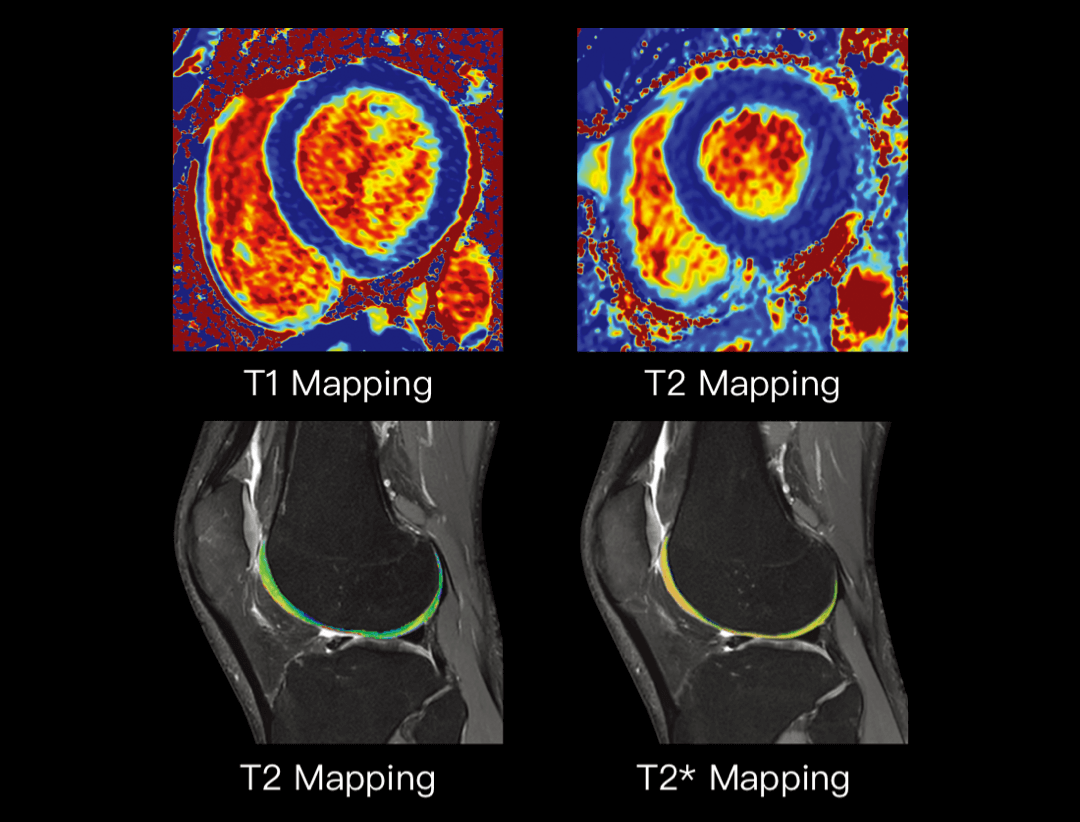

参数定量

精确计算时间参数图,为各脏器病变提供临床及科研所需的定量数据。